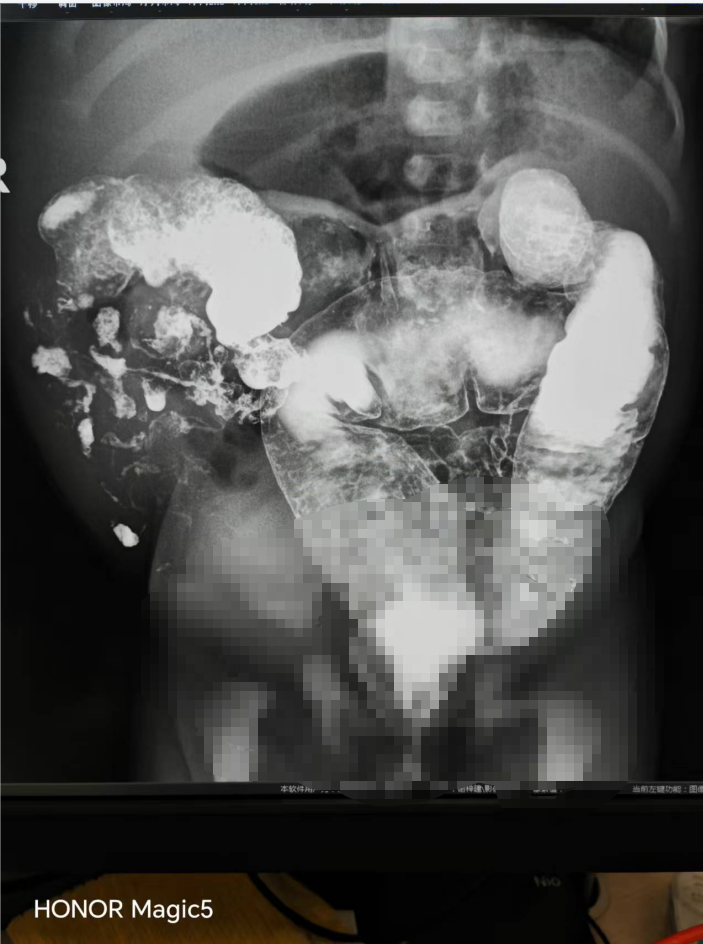

患儿钡灌肠造影-先天性肠旋转不良(回盲部及肠管分布异常)